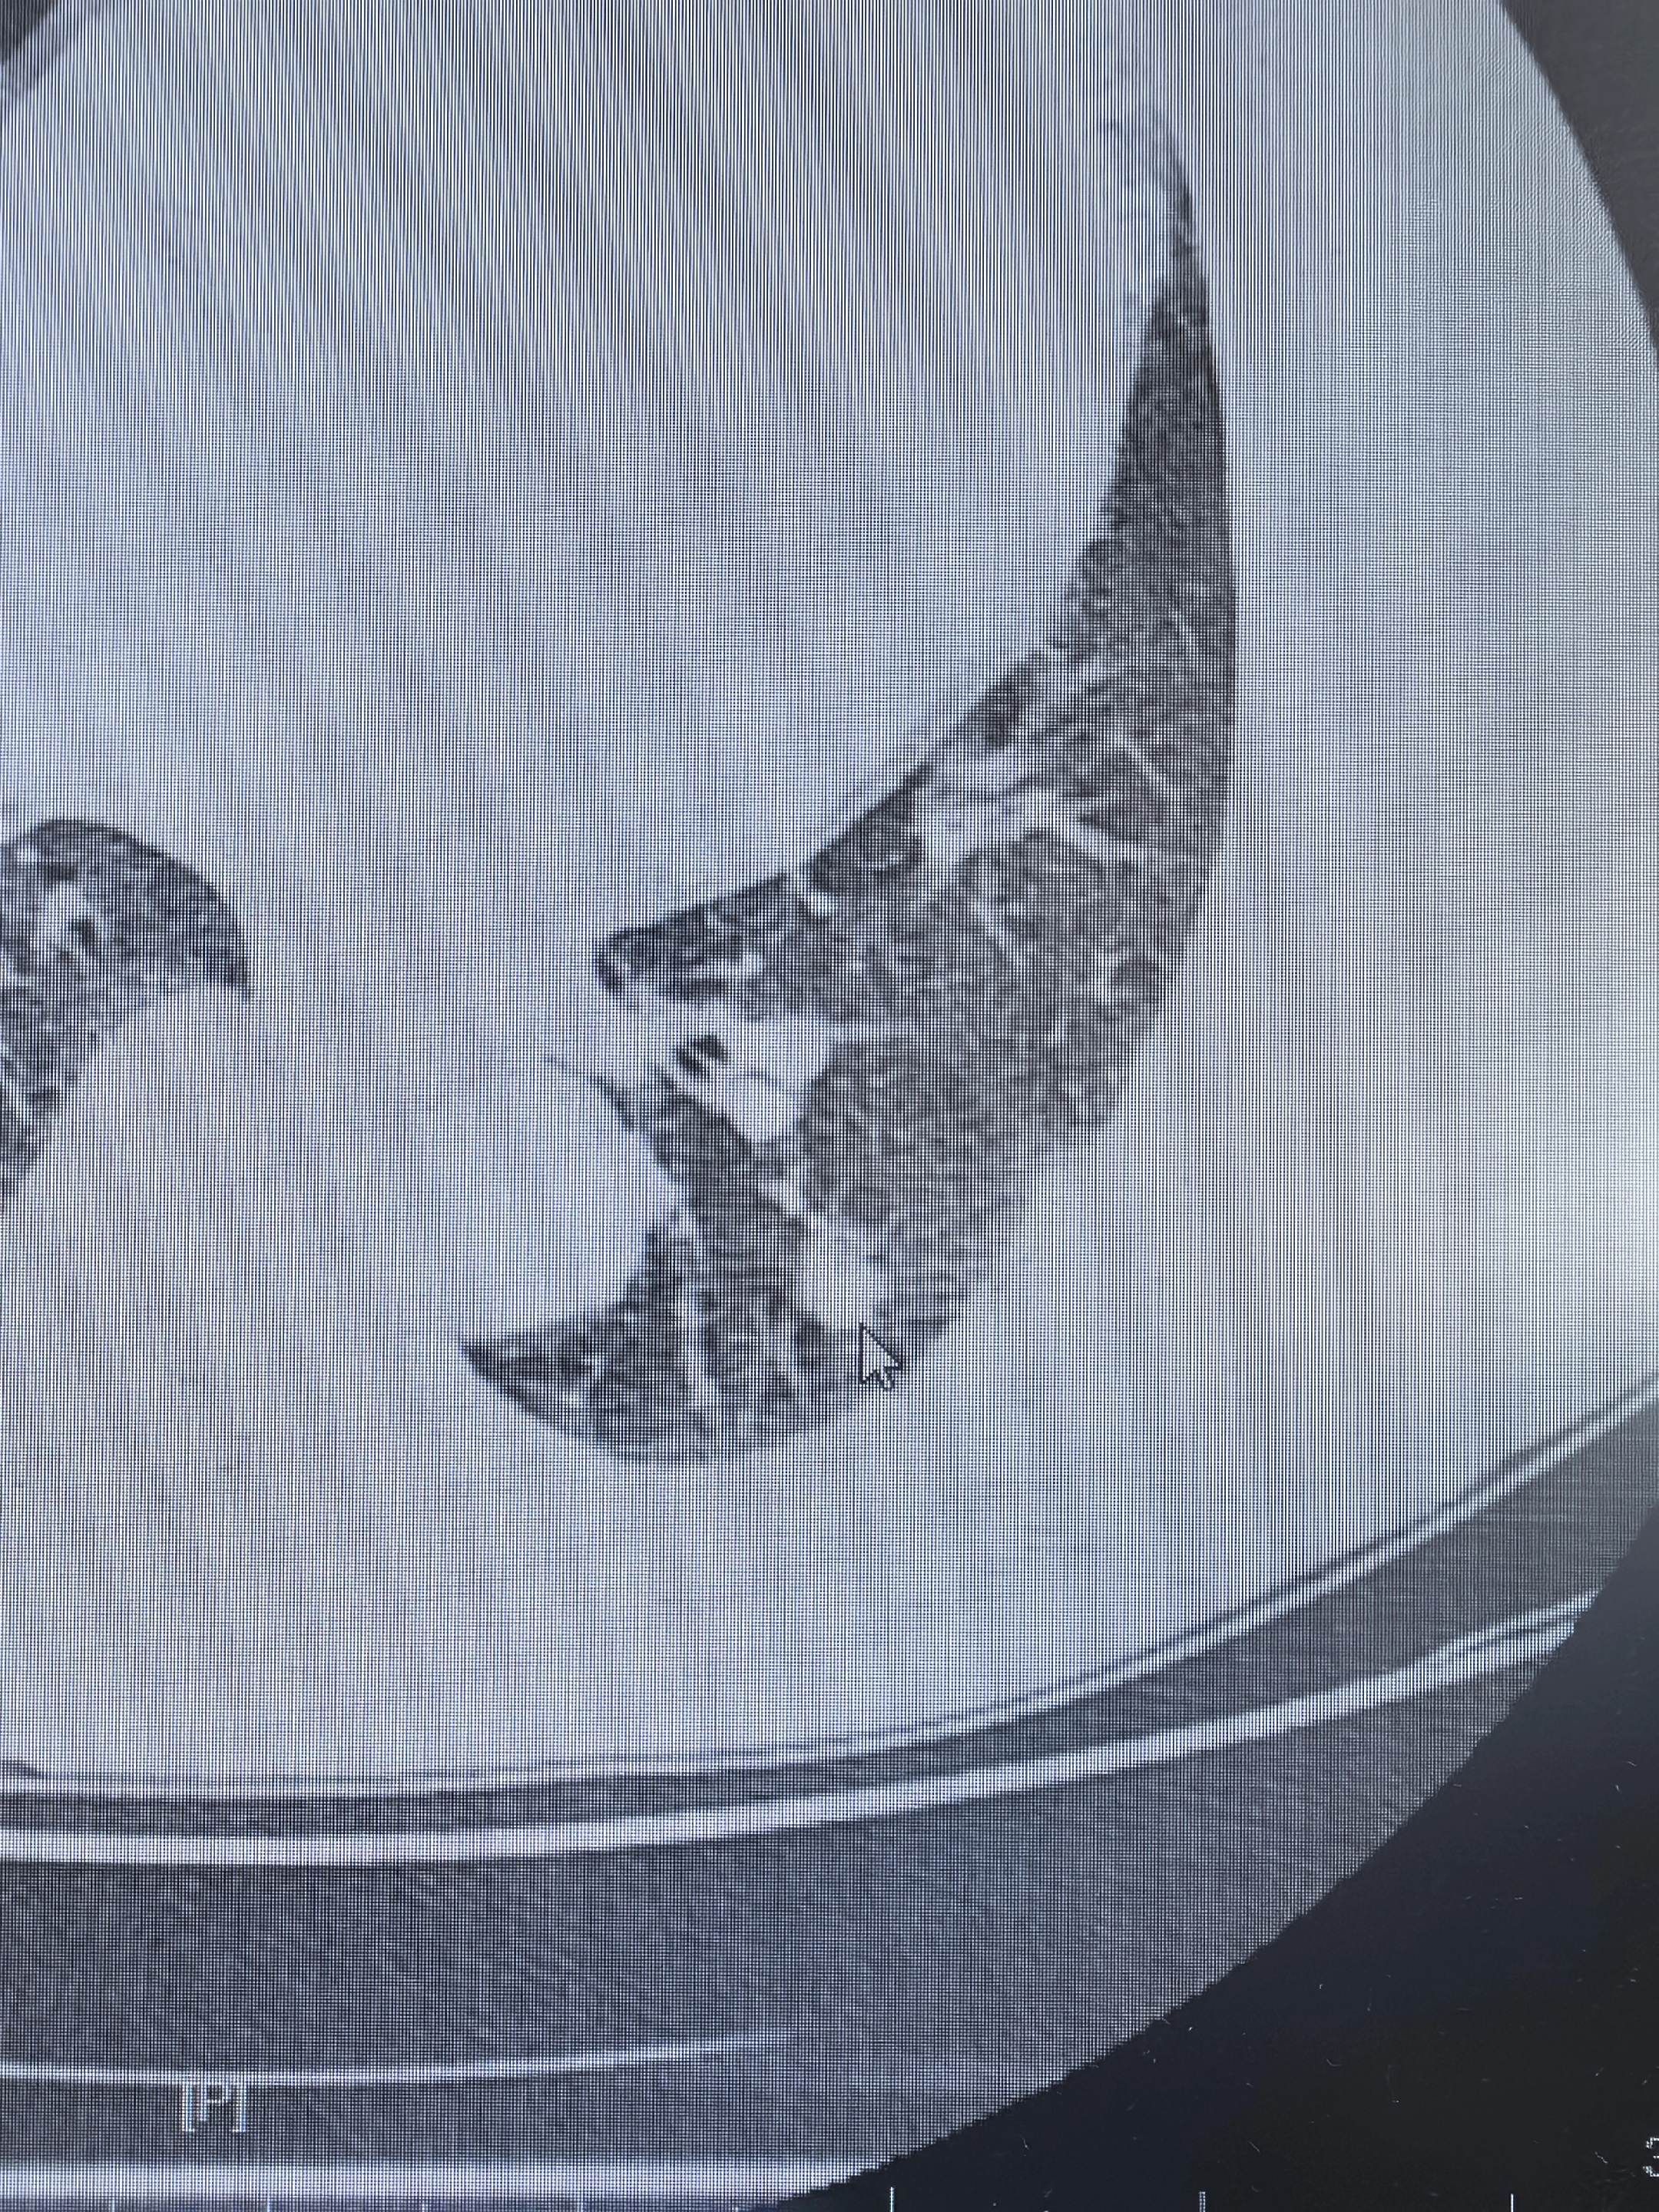

左下肺实性肺癌。左下肺实性肺癌,清扫了第4-14组淋巴结……对于实性的肺癌,系统性清扫淋巴结是非常有必要的……手术时间一个小时……

左下肺实性肺癌。左下肺实性肺癌,清扫了第4-14组淋巴结……对于实性的...